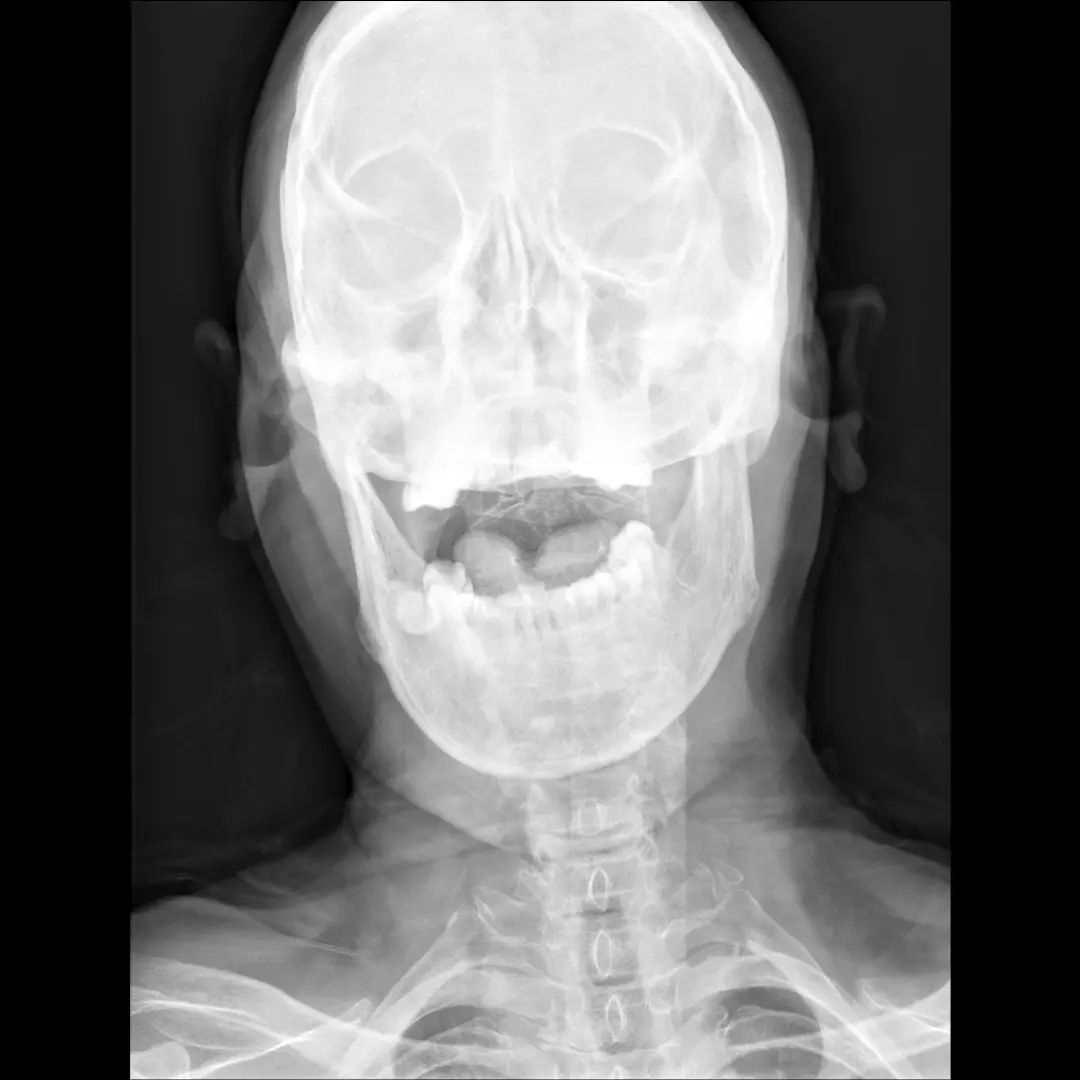

经过全程监护和系统治疗,患者术后恢复良好,骨折解剖复位,复查X线及CT显示固定位置佳,术后3天下地行走,术后4天即出院回家休养。

“宝剑锋从磨砺出,梅花香自苦寒来。”目前,枣庄市立医院脊柱外科在上颈椎损伤治疗方面取得长足发展,对于枢椎齿状突骨折,已能独立开展前路空心螺钉固定、后路Margerl手术、后路椎弓根钉棒固定术,在上颈椎外伤治疗方面处于省内领先。

颈椎骨折脱位前后联合减压固定术